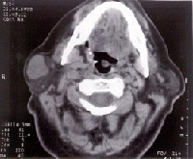

Parotid Pleomorphic Adenoma, we clearly observe the normal parotid parenchyma and the mixed tumor (white) that bulges in the subcutaneous

The clinical diagnosis is completed with the aspiration puncture that gives us the diagnosis and the computerized axial tomography that defines its extension and neighborly relations. The treatment is surgical and always requires a parathyroidectomy-type approach, identifying the facial nerve at its exit from the stylomastoid foramen, following it to its terminal branches, if the lesion is limited to the superficial lobe, a suprafacial or superficial lobe parotidectomy is performed, but if the tumor affects the deep lobe, we will require total parotidectomy, always having to respect the facial nerve. The lesion that affects the submaxillary gland must be cleaved in its entirety including the tumor preserving the mandibular branch of the facial. The recurrence of these lesions is usually due to insufficient resection, and must include in the second wide margins of tissue, to prevent additional recurrences, in these patients it may be inevitable to sacrifice branches of the facial nerve, in certain cases suture or nerve graft is indicated.